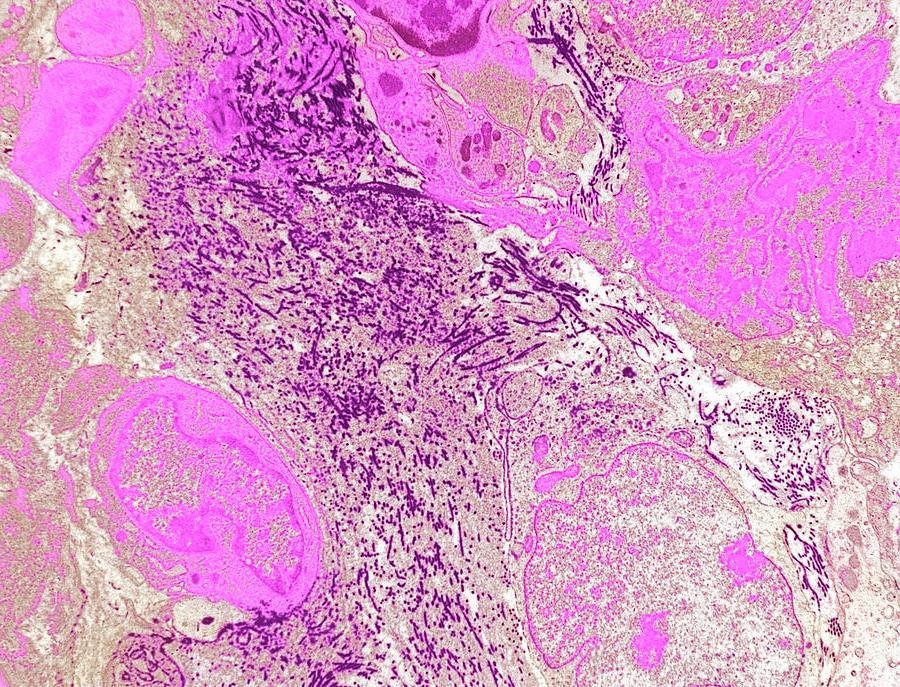

A biopsy is usually essential to confirm whether a mass is a sarcoma and, if so, what subtype and grade it is. In many cases this is done as a core needle biopsy, planned carefully so that the biopsy track can be removed during surgery if needed.8